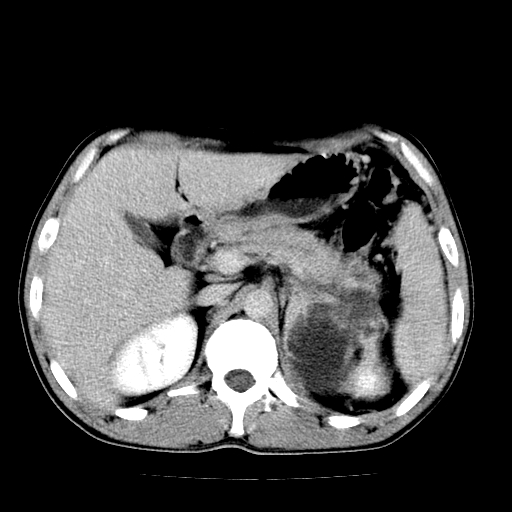

以下是引用天南地北在2007-4-30 13:36:00的发言:[br]支持慢性胰腺炎伴有假性囊肿

以下是引用andymaomao在2007-4-30 14:28:00的发言:[br]支持:1.慢性胰腺炎并假性囊肿形成可能;[br] 2.左肾形态稍增大,旋转不良。